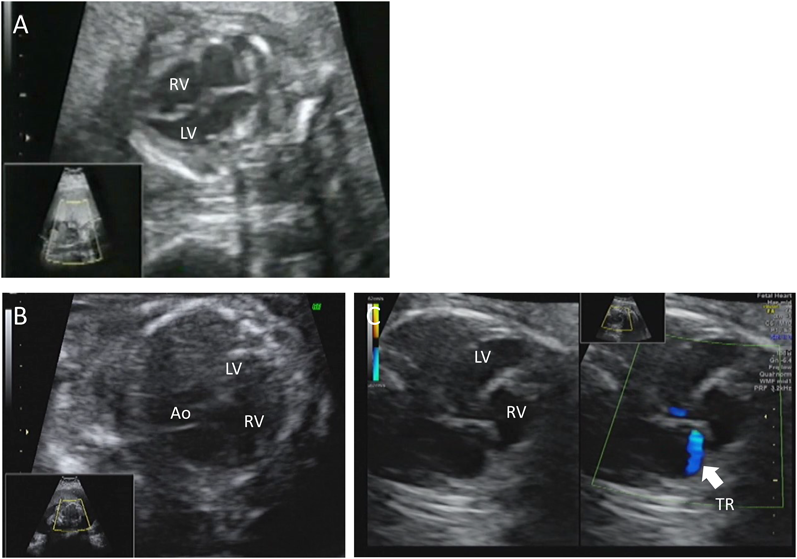

胎児期より拡張型心筋症と診断され周産期死亡した兄弟例Fetal Sibling Case of Familial Dilated Cardiomyopathy